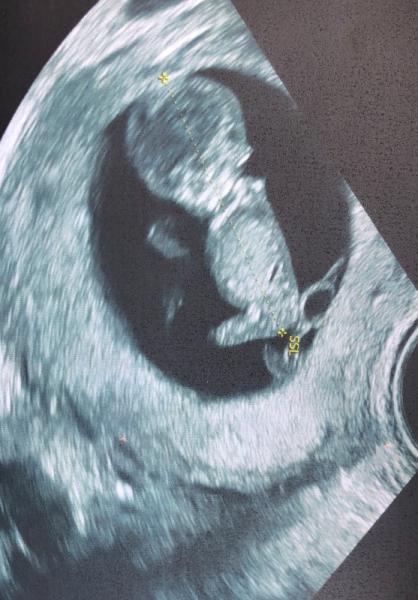

Hallo ihr Lieben heute hatte ich mein erstes großes Screening. Ich habe so einen lieben Arzt, der berechnet das noch nicht Wir haben heute grob geschaut und schauen in zwei Wochen nochmal genauer. Weil ich erst am Ende der 11. Woche bin, sieht man da wohl nochmal alles deutlicher. Aber es sah so schonmal alles ganz gut aus. Hat keine Nackenfalte gesehen, Rücken und Bauch sind zu. Ich bin der Meinung, dass ich einen kleinen Pipimann gesehen habe, aber er sagt, jetzt kann man da noch nichts sehen Das schönste war, dass mir mein kleines Baby gewunken hat ich glaub, das war bisher der emotionalste Moment und tröstet über die Beschwerden hinweg. Als Belohnung gab es eine erste Umstandsmode. Ganz schön kompliziert, Undtandsmode zu kaufen. Dafür sollte es mehr Läden geben Ich hab euch die Bilder mal beigefügt. Eins ist sogar in 3D Mittwoch hab ich dann wieder Wochenwechsel :)

Bild zu 1. Trimester Screening - Forum für Januar - Mamis

Und das zweite Bild